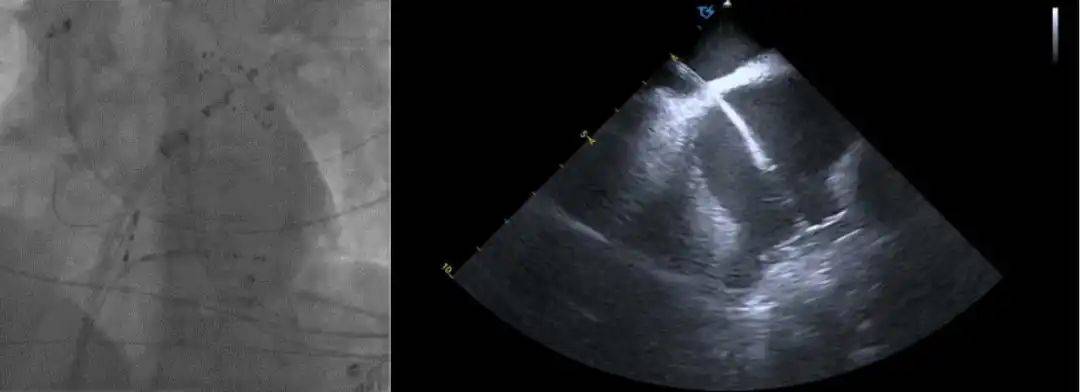

术前术后心包对比:

术前心包基线扫描

术后心包检查